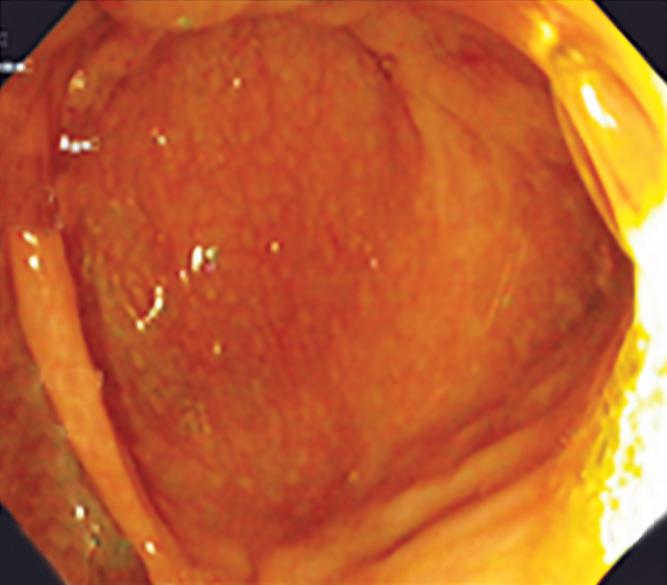

Redefiniendo la evaluación endoscópica

inicial

de los síntomas esofágicos: hacia un paradigma diagnóstico basado en la precisión

Redefiniendo la evaluación endoscópica inicial de los síntomas esofágicos

Introducción

Dadas las limitaciones del paradigma actual, existe una sólida justificación para renovar la conceptualización del rol de la endoscopía índice en la evaluación de los síntomas esofágicos. La endoscopía ya es un punto final inevitable para la mayoría de los pacientes debido a síntomas de alarma, enfermedad refractaria o incertidumbre diagnóstica.1 Aprovechar esta endoscopía índice para realizar una evaluación fisiológica bajo sedación ofrece múltiples ventajas.

En primer lugar, la endoscopía proporciona información anatómica y mucosa crítica que contextualiza los hallazgos fisiológicos. La graduación de la esofagitis mediante la clasificación de Los Ángeles, la evaluación de EoE con biopsias sistemáticas y puntuación EREFS, la valoración de la válvula gastroesofágica y de la hernia hiatal, así como la identificación de signos endoscópicos sugestivos de acalasia, aportan elementos fundamentales para la interpretación integrada de los datos fisiológicos posteriores.8